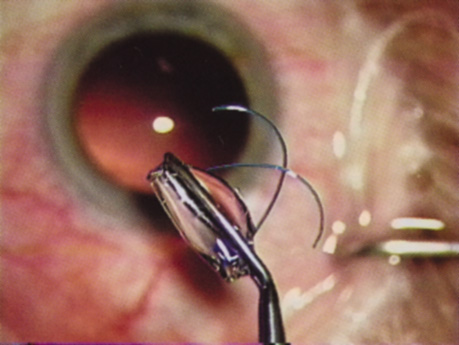

ANTERIOR CAPSULOTOMY

One of the most beneficial techniques developed over the last decade is capsulorrhexis. A continuous curvilinear anterior capsular opening helps prevent intraoperative and postoperative complications. With capsulorrhexis, mechanical strength of the capsular opening is superior to that in a can-opener capsulotomy; thus, a tear to the posterior capsule with subsequent vitreous loss is much less likely.96 Capsulorrhexis allows for nuclear manipulation with less risk of posterior capsule rupture. Cortex removal is made easier as well, because it becomes easier to differentiate cortical material from anterior capsule. Should a posterior capsular tear occur, sulcus fixation is more likely attainable with the presence of a clearly visible residual anterior capsular rim. Placement of both IOL haptics into the capsular bag is more certain with capsulorrhexis because the surgeon can more easily visualize the haptics gliding beneath the anterior capsular rim.

Capsulorrhexis can be performed with a cystitome, capsulorrhexis forceps, or combination-type instruments. Regardless of which instrument is used, several principles can help the surgeon successfully complete capsulorrhexis. It is important to maintain the anterior chamber, because making the chamber shallow increases tension on the zonules and causes the tear to run peripherally. The authors recommend the use of a viscoelastic agent for maintaining chamber depth and, of course, for endothelial protection. Therefore, if the tear begins to run peripherally, the surgeon should redeepen the anterior chamber before attempting to redirect the tear. Additionally, folding the capsule margin can aid the surgeon in redirecting the tear more accurately (Fig. 10).

Fig. 10. The capsulorrhexis tear is more easily redirected by folding the capsule over, in advance of the tear.